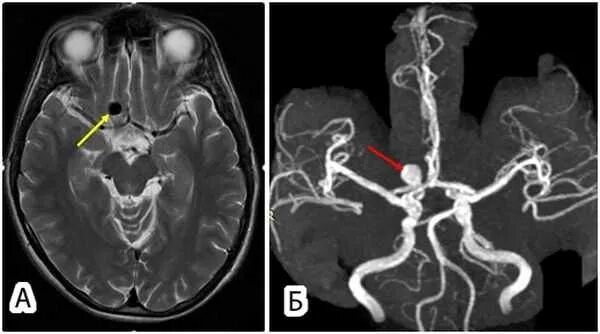

Аневризма головного мозга на кт